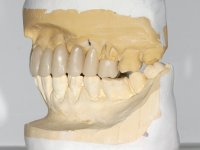

The patient was proposed to undergo a fixed oral rehabilitation consisting of a 2-element bridge over teeth 11 and 21 and a 5-element bridge over 3 implants that would be placed in the location of teeth 22, 24 and 26. The prosthetic structures would have an infrastructure in Zr coated with ceramic and the bridge over the implants would be screwed. The indicated extraction of teeth 25 and 26 and placement of an implant in the 26 site would imply surgery to fill the maxillary sinus. As the patient showed interest in having fixed temporary rehabilitation during treatment, we divided the treatment into 6 phases to achieve this goal: 1- Placement of a temporary bridge over teeth 11,21,25 and 26. With tooth extraction 24. 2- Placement of 2 implants in the location of teeth 22 and 24. 3- Placement of a temporary 6-element bridge over teeth 11 and 21 and over the implants. 4- Carrying out surgery to fill the maxillary sinus. 5 – Placement of the implant in the location of tooth 26 and in the area where the filling of the maxillary sinus was made. 6 – Placement of the definitive work.

A temporary acrylic bridge made in the laboratory with 7 elements was made, with teeth 11,21, 25 and 26 as pillars. The old bridge was removed and tooth 24 was extracted. The provisional bridge after relining was cemented in the mouth. Two implants were placed in the teeth 22 and 24 and 3 months after this intervention an impression was made to make a temporary bridge screwed over the implants and cemented to the teeth. The bridge was placed in the mouth and teeth 25 and 26 were extracted. 3 months later, surgery was performed to fill the maxillary sinus and 6 months later the implant was placed in the location of tooth 26. After osseointegration of this implant, the final impression was made for the final work. The bridge over the implants was permanently screwed on and the bridge over the teeth was cemented with resin-reinforced glass ionomer cement.